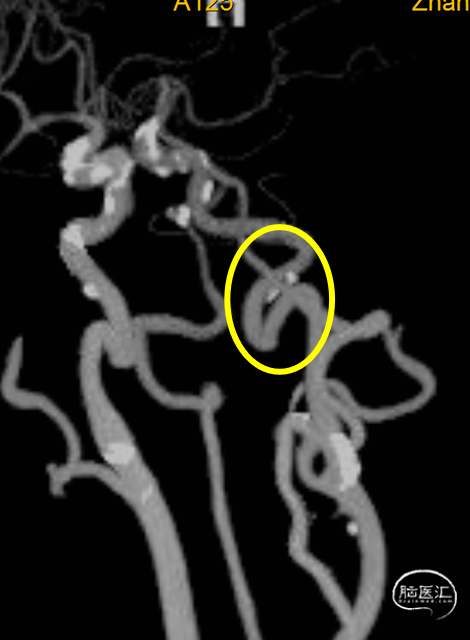

动脉早期冠状位残端

动脉早期水平位残端

动脉晚期冠状位脑膜支逆流

动脉晚期矢状位脑膜支逆流

残端平齐,造影剂渗透征,晚期分叉处不能显影,考虑栓塞性病变,眼动脉段角度大,可尝试大内径导管先抽吸或抽拉结合。